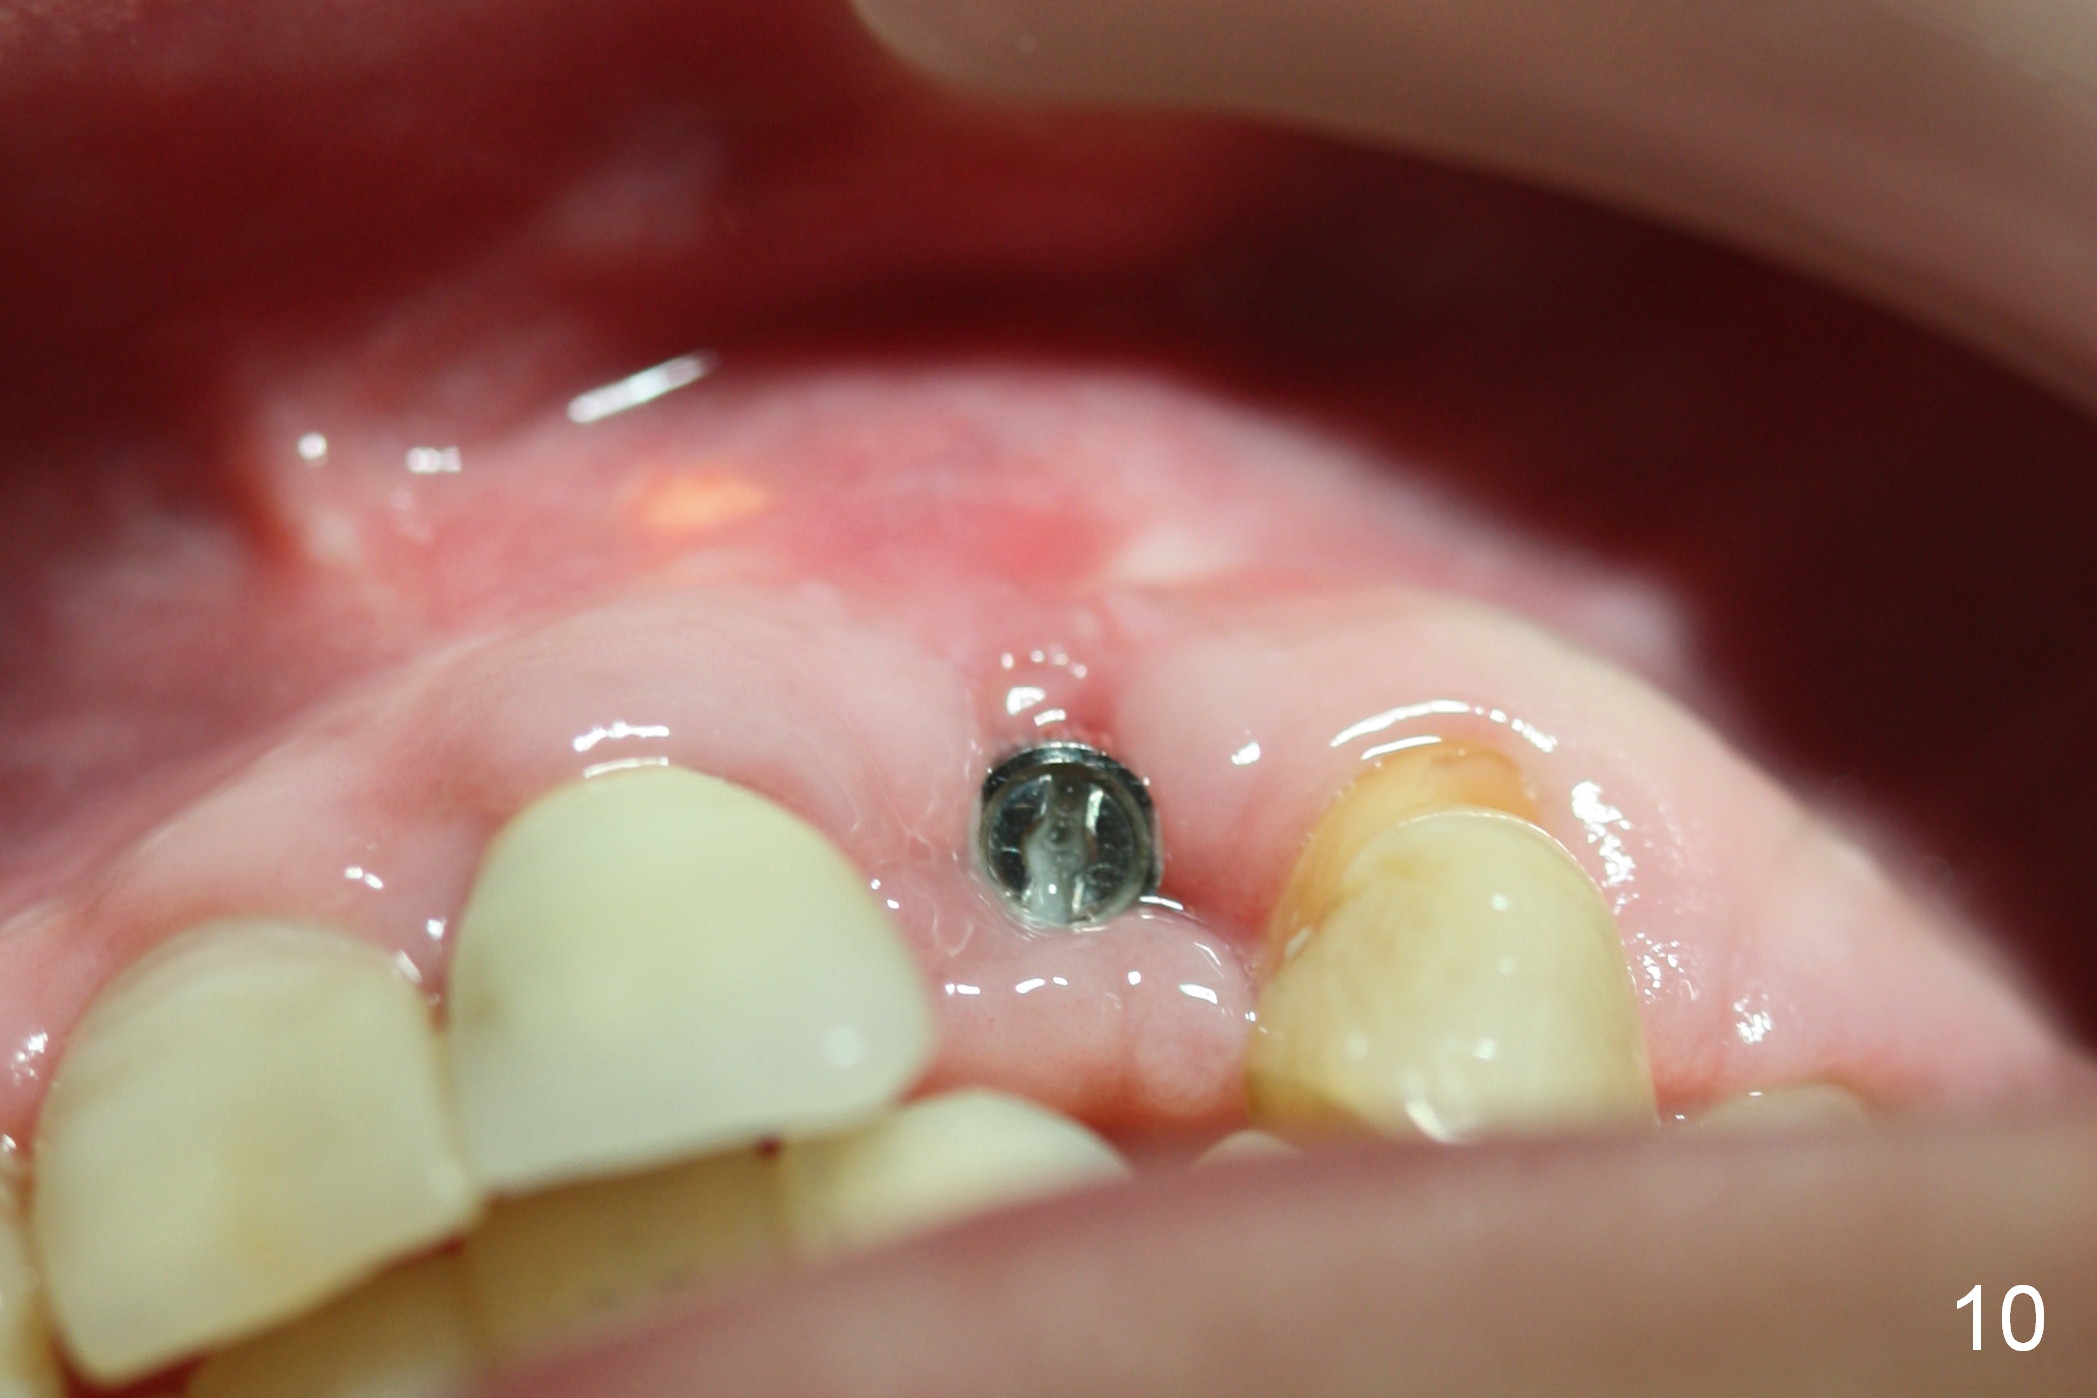

As expected, there is midbuccal tissue deficiency (Fig.9,10: 2 months postop). After discussion, a free gingival graft from the palate is placed (Fig.11,12 *). Two weeks later, the graft sloughs (Fig.13). A pedicled flap is designed (Fig.14) and transferred to repair the defect (Fig.15,16).